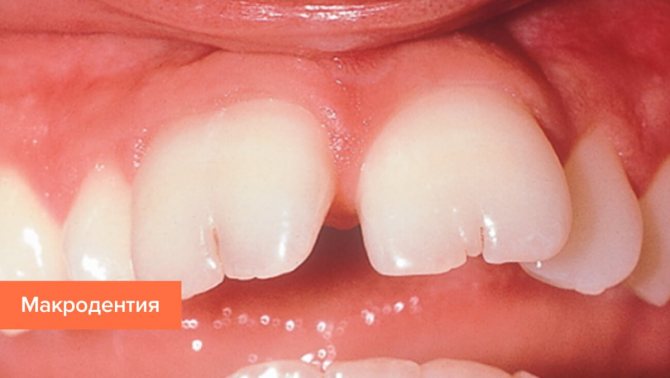

Аномалии размеров зубов подразделяются на макро- и микродентию.

В первом случае видимые части зуба имеют слишком большие размеры, которые никак не совпадают с нормой. Наиболее распространена эта проблема с центральными верхними резцами. Слишком крупные зубы могут мешать остальным зубам, они не оставляют для них места и тем самым портят общий внешний вид. Кроме этого зубы такого размера плохо влияют на гармонию черт лица и относятся к косметическим недостаткам. Вылечить их невозможно, поэтому они просто подвергаются удалению. После чего проводится исправление соседних зубов, а появившийся дефект скрывают путем протезирования или имплантации.